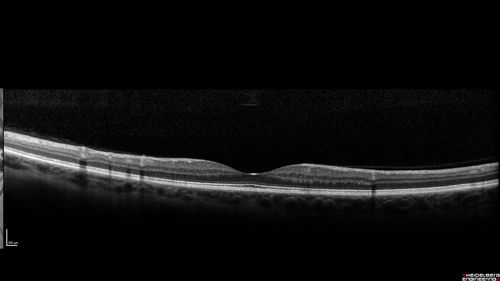

Foveal Red Spot Syndrome Left Eye

She noticed on covering the right eye that she had distortion off center in the left eye a few weeks ago.  She had a temporal paracentral scotoma intermittently visible on the eye examination.  She does notice that the left eye is not as good as the right eye now that it has been brought to her attention.  She has every now and then a little twitch in the left eye.  She has no pain on eye motion.

VA OD: sc20/20 NccJ1+

VA OS: sc20/20-1